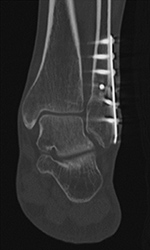

Hardware Failure. Sagittal multiplanar reformation demonstrates fractured pedicle screw in patient with treated vertebral compression fracture and sudden onset of worsening back pain.